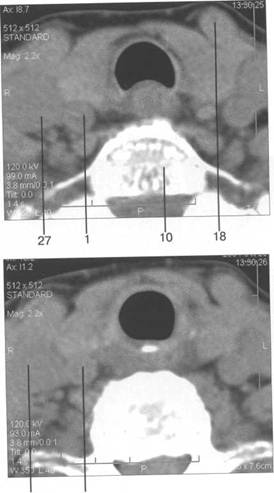

13 26 4.1 16

27 1

8 15 13 26 41 18 16

железы

хряща.

1

10 26 41

8 24 16 |

MPT

17 8 1 7 16 |